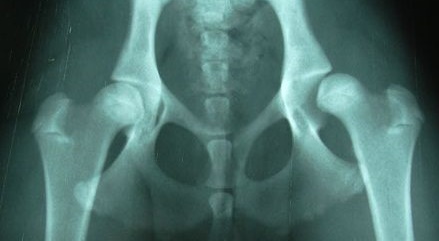

Диагностика вывиха бедра обычно не вызывает затруднений у травматолога. С целью уточнения положения головки бедренной кости, а также исключения возможных костных повреждений пациенту выполняется рентгенологическое исследование в двух проекциях либо магнитно-резонансная томография тазобедренного сустава.

В травматологии принято выделять задние и передние вывихи бедра. В свою очередь, передние вывихи разделяют на передненижние (запирательные) и передневерхние (надлонные), а задние - на задненижние (седалищные) и задневерхние (подвздошные).